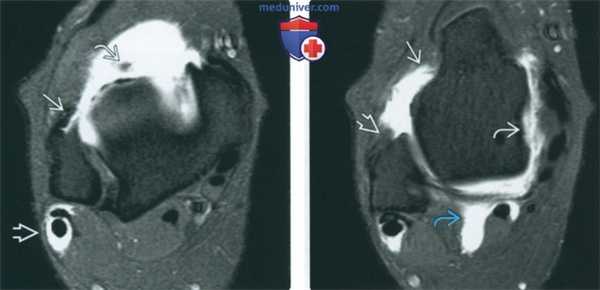

(Слева) МР-артрография в режиме Т1ВИ FS, аксиальный срез: определяется разрыв ПНМС. Наличие жидкости во влагалище сухожилий малоберцовых мышц обусловлено разрывом пяточно-малоберцовой связки. В увеличенном переднем завороте визуализируется свободное тело.

(Справа) МР-артрография в режиме Т1ВИ FS, аксиальный срез, проходящий ниже: определяется распространение жидкости вдоль шейки таранной кости через дефект в ПТМС (видна ее культя). Жидкость распространяется через дефект в глубоком слое дельтовидной связки. Наличие жидкости во влагалище сухожилия длинного сгибателя большого пальца не является признаком патологических изменений.